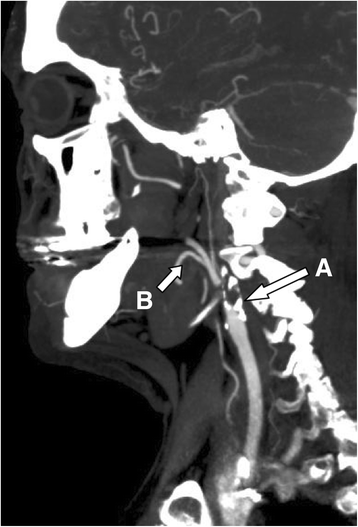

A 64-year old man with known arterial hypertension, hypercholesterolemia, a 40 pack-year history of smoking and alcohol abuse, developed recurrent exercise-induced weakness associated with high-frequency irregular tremor in his right arm. In the beginning, the patient only experienced the symptoms during running/brisk walking. The patient later progressed to experience the symptoms during light walking. These shaking spells lasted for several minutes, but without other associated neurological deficits. MRI of the brain revealed no signs of acute ischemia in the left hemisphere, but bilateral subcortical white matter lesions, suggestive of small vessel disease, were present (Fig. 1). The left internal carotid artery (ICA) was occluded at the bifurcation (Fig. 2), but there were no additional stenoses or occlusions in the remainder of the cervico-cranial vasculature. The left middle cerebral artery (MCA) was reperfused from the circle of Willis due to anterior cross filling. On first admission, he was on no antihypertensive medication and had a blood pressure of 135/91 and a heart rate of 91.

Initial CT-angiography showing left carotid occlusion. CT-angiography of the left carotid artery demonstrates calcified plaque of the left carotid bulb with atherosclerotic occlusion of the internal carotid artery (a). Of note the left external carotid artery is patent and there is robust filling of its branches (b)